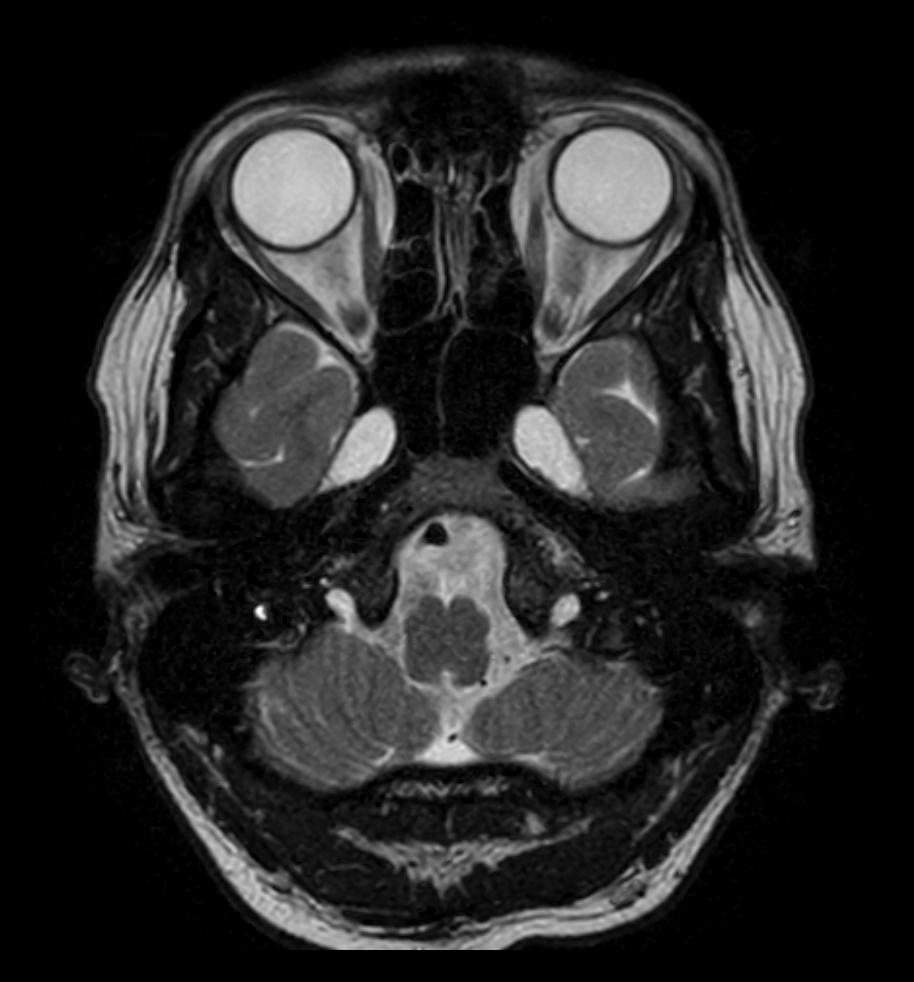

T2w TSE - MultiVane XD